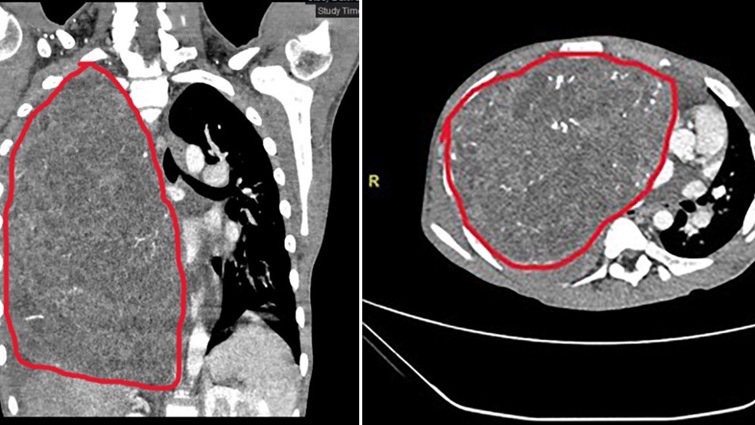

小宇体内的纵膈肿瘤尺寸达29×27×15厘米,长满右侧胸腔并延申到左侧,将腹黑从平标的置挤压到左侧胸壁旯旮,并严重压迫邻近脏器、影响心肺功能。更辣手的是,肿瘤血供丰富,与周围组织粘在一齐,手术切除风险极高,极易激发致命性大出血。

2026年3月13日,麻醉科郭东东副主任大夫及团队全程严实护航,丁建勇讲解和复旦儿科心怀外科张文波副主任大夫密切协作,紧密操作,逐层剥离,最终生效将肿瘤无缺切除,术中出血不到100ml。切下的肿瘤重达7斤3两,跳动了成年东说念主头颅大小。术后小宇心肺压迫即刻铲除,班师转入康复休养,并于近日班师出院。